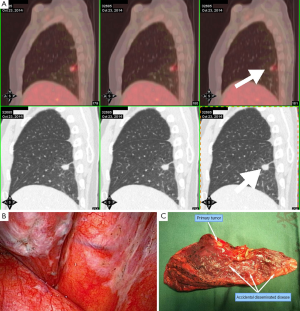

Veronesi et al. (14) found that slow-growing or indolent lung cancers comprised approximately 25% of incident cases, many of which may have represented overdiagnoses. In addition to early-stage cancers, this study indicated that slow-growing forms occur in lung cancers considered “advanced disease”. As shown in Figure 3, a 37-year-old female non-smoker was diagnosed with a right lower lobe lung cancer, cT1bN0M0 stage 1a, during a preoperative workup for uterine fibroid surgery. Video-assisted thoracic surgery (VATS) found multiple nodules (1-3 mm) distributed on the surface of the visceral and parietal pleurae. A right lower lobectomy and mediastinal lymph node dissection was performed, and the patient was ultimately diagnosed as pT4N0M1a stage IV. There were no visible lesions by CT scan and the patient was asymptomatic. After fully informing the patient, she was closely followed with no disease progression for 2 years, indicating that some pT4N0M1 lung cancers are slow growing and even indolent in terms of volume doubling time (VDT).